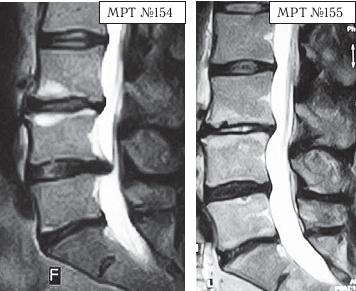

Приведу ещё пример, связанный с результатами лечения методом вертеброревитологии.

На МРТ № 154 наблюдается состояние поясничного отдела позвоночника после двух операций в сегментах LIII-LIV и LV-SI секвестрированная грыжа межпозвонкового диска в сегменте LIV-LV, абсолютный стеноз спинномозгового канала.

На МРТ № 155 — состояние поясничного отдела позвоночника после лечения методом вертеброревитологии.